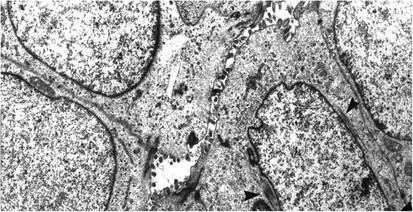

Ultrastructure

Ultrastructurally, all the cells of the tumor are uniform and are thus of one cell type. They have irregularly clefted nuclei with nucleoli. The cytoplasm contains few organelles, including small numbers of mitochondria, lysosomes and Golgi apparatus. Rare cells contain stacks of confronting cisternae of rough endoplasmic reticulum. The cells are attached one to each other by well-formed desmosomes. Interestingly, at the ultrastructural level, even the areas with a solid appearance at the light microscopical level reveal a microcribriform arrangement. The secretory spaces are composed of well-formed microvilli on the apical borders of the cells. A further unusual feature is that many of the secretory cells displaying the apical microvilli also contain groups of microfilaments in the cytoplasm. These cells thus had features of hybrid myoepithelial-secretory cells, and had thus all aspects of 'secretory myoepithelia'. Many cells, especially those in areas, which showed spindling of neoplastic cells, are found to contain numerous bundles of cytoplasmic tonofilaments (Figure 10). Presence of secretory myoepithelial cells in CAMSG seems to be almost unique83, 84 with exception of very rare mucinous myoepithelial tumors that may contain abundant intracellular mucin.92